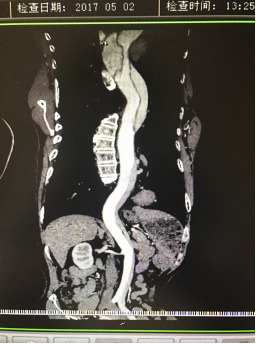

5月2號劉大伯照常早起干活,突然胸部劇烈疼痛,難以忍受,全身大汗,同時伴有右上肢發(fā)涼,他心想這次心絞痛比之前嚴重的多啊,趕緊叫上孩子到吉林國文醫(yī)院心血管內科住院,患者長期高血壓病史,血壓一直控制不理想,大夫給他做了檢查,測左上肢血壓:82/45mmHg,右上肢血壓測不出,心率52次/分,右側肱動脈、尺動脈、橈動脈搏動消失,左側股動脈搏動較右側弱。“糟了,雙側血壓差別這么大,是不是主動脈夾層了?”,接診大夫趕緊找來李主任,李主任反復詢問患者病情,表情突然凝重起來,患者胸痛這么明顯,血壓低的厲害,主動脈夾層的可能性很大。二話不說,李主任立即聯系影像科的醫(yī)生準備做主動脈CTA,移動患者做檢查的過程大夫們非常小心,嚴密監(jiān)測患者血壓變化情況。兩個小時后結果出來了,主動脈夾層從升主動脈一直撕裂到左側髂總動脈?。?!

從開始學醫(yī)到現在已經快9年了,主動脈夾層患者也見過一些,但像劉大伯這種危險類型的還是第一次見到,心里真的為他捏把汗,撕裂的主動脈隨時都有可能破裂,生命隨時可能終止,要知道主動脈夾層的死亡率非常的高,約50%的患者發(fā)病后48小時死亡,約90%的患者發(fā)病1個月內死亡。